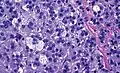

Histopathology

The microscopic histopathology analysis of the tissue samples obtained from the adrenal cortex of individuals presenting with adenoma-associated symptoms such as primary aldestronism (PA) indicates that adenoma cells are relatively larger with different cytoplasm, and increased variation in nuclear size. This indication is based on comparison between the healthy (normal) and affected (adenoma-associated) adrenal cortex tissue samples.

- Adrenocortical adenoma with focal high grade nuclear atypia

- Adrenocortical adenoma with focal necrosis

Adrenocortical adenomas are most commonly distinguished from adrenocortical carcinomas (their malignant counterparts) by the Weiss system,[10] as follows:[11]